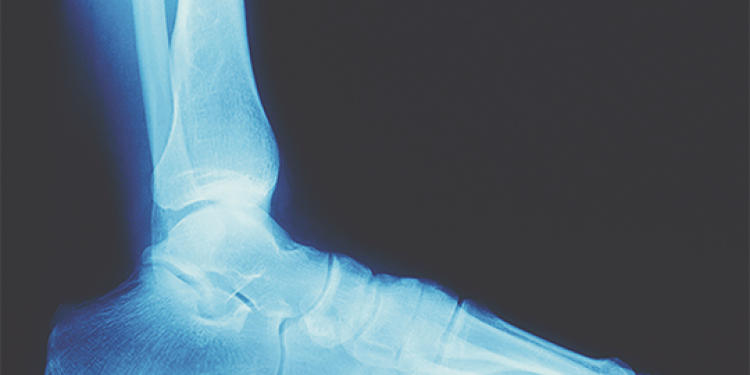

• Ankle sprain: When the ankle twists or the foot rolls on its side, the ligaments that support the ankle joint can stretch and tear. Swelling and pain usually occur on the outside of the ankle within minutes to a few hours of the injury, depending on injury severity. Because it may be impossible to differentiate an ankle sprain from an ankle fracture without an x-ray, particularly if the pain in the ankle makes putting weight on it unlikely, a visit to an orthopedic doctor may be necessary.

• Broken bones: Bone fractures often happen during collisions with other players or from falls. Sometimes a fracture is obvious, but not always. A snap or grinding sound at the time of injury often signals a fracture, says VCU Health. If there’s a break in the skin and the bone is showing, or the athlete cannot bear weight or use the extremity after 15 minutes, an X-ray is likely.